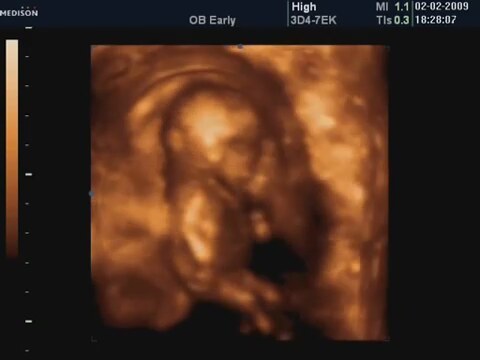

18 Haftalik Bebeğin 4 Boyutlu Ultrason Görüntüsü